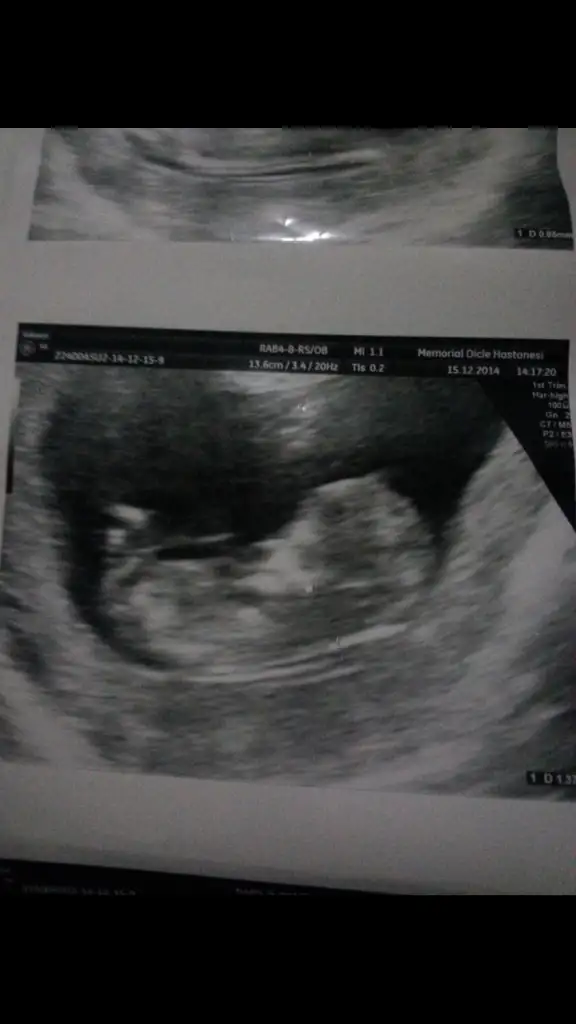

minecan 15 e kadar sakladı içim hep kız diyo kızsa azıcık cadı sen merak ettikçe saklıyo :)

Canim insallah kizdir..)) face koyabilirsin elbet,doktor once erkek dedi sonra kiz gibi dedi tam goremedigi icin bisey soylemiyecegim dedi..)) iyice merakta birakti beni.. Suan 17+4 gunluguz yarin yine kontrol var bakalim bu defa gorecekmi simdiden saol canim

Minecan anam çok heycanli ya yarin çikolata yede git Dr tamam hemen haber et bak ben koz diyorum pipi olsa görünürdü bea .senden arkadasim bence kizin yolda seninde